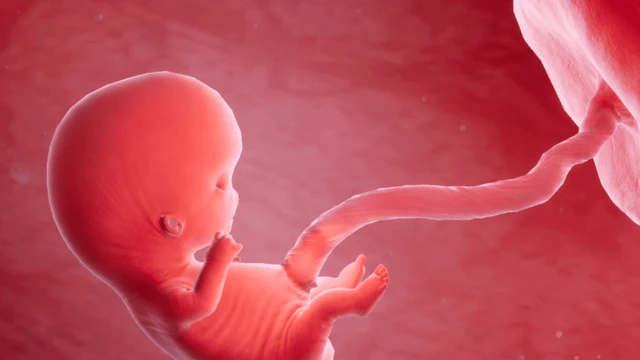

Thai bị thiếu máu là một trong những tình trạng y khoa đáng lo ngại trong thai kỳ, có thể dẫn đến nhiều biến chứng nghiêm trọng như suy tim thai, phù thai, thậm chí là đe dọa tính mạng của thai nhi nếu không được phát hiện và can thiệp kịp thời.